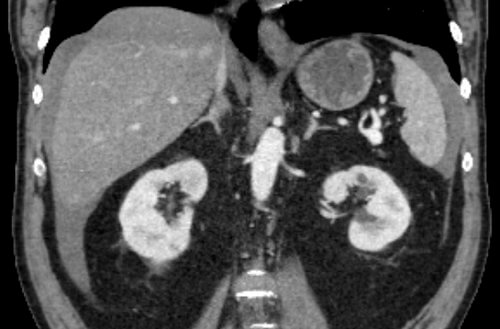

36 year old female with no significant past medical history who presents to the ED with right lower quadrant pain who underwent a CT scan for further evaluation.

36 year old female with no significant past medical history who presents to the ED with right lower quadrant pain who underwent a CT scan for further evaluation.